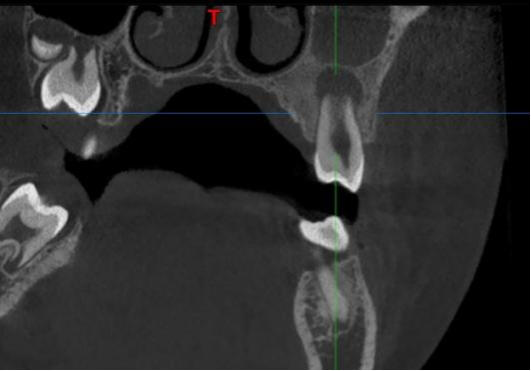

辅助检查:CBCT显示25牙根尖呈喇叭口样敞开,未发育完全,根尖低密度暗影。

CBCT冠状面显示25牙根尖未发育完成,根尖阴影